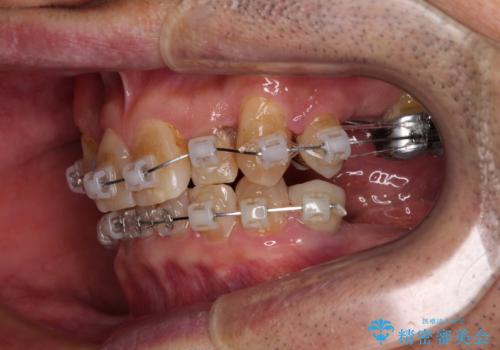

奥歯の欠損と前歯のデコボコを治したい インプラントと矯正治療の総合歯科治療

- クリアブラケット

奥歯に欠損が多く、矯正治療はやや難航することが予想されますが、患者様の希望もあり、上顎左右小臼歯を1本ずつ抜歯し、ワイヤー装置にて矯正治療を行うこととしました。

矯正歯科治療を行うに当たり、痛みや違和感を感じている歯の根管治療を行い、矯正治療中にインプラント埋入し、補綴治療と矯正治療を同時に終了できるように進めて行くこととしました。

銀歯やむし歯治療されている歯を抜歯する治療計画としたため、やや時間はかかりましたが、治療後の仕上がりには大変満足していただけました。